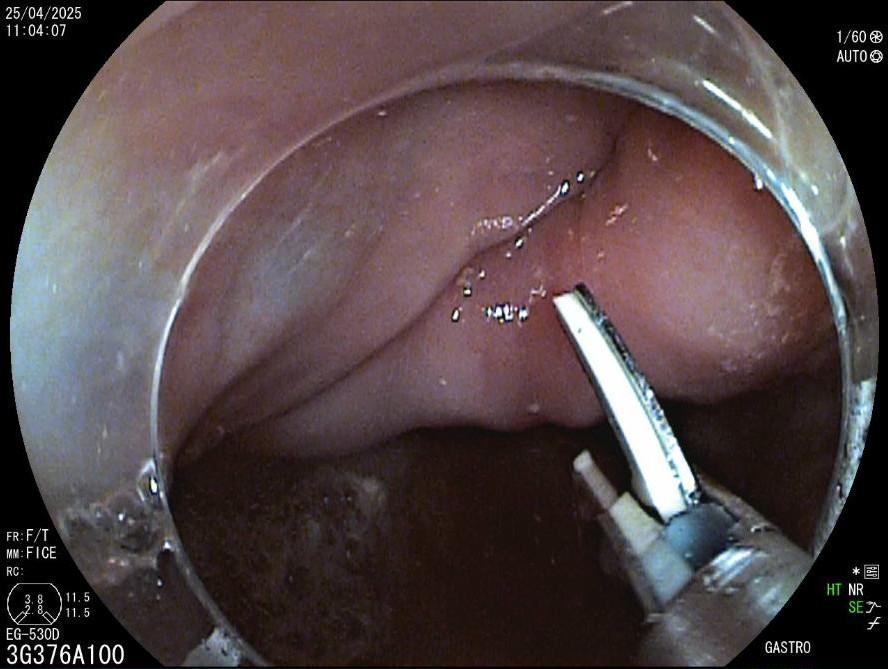

La evaluación endoscópica reveló un divertículo de Zenker de 3 cm, con retención significativa y acumulación de saliva y restos de comida (fig. 1). Se consideró que el paciente no era apto para la cirugía y se planificó una septotomía endoscópica.